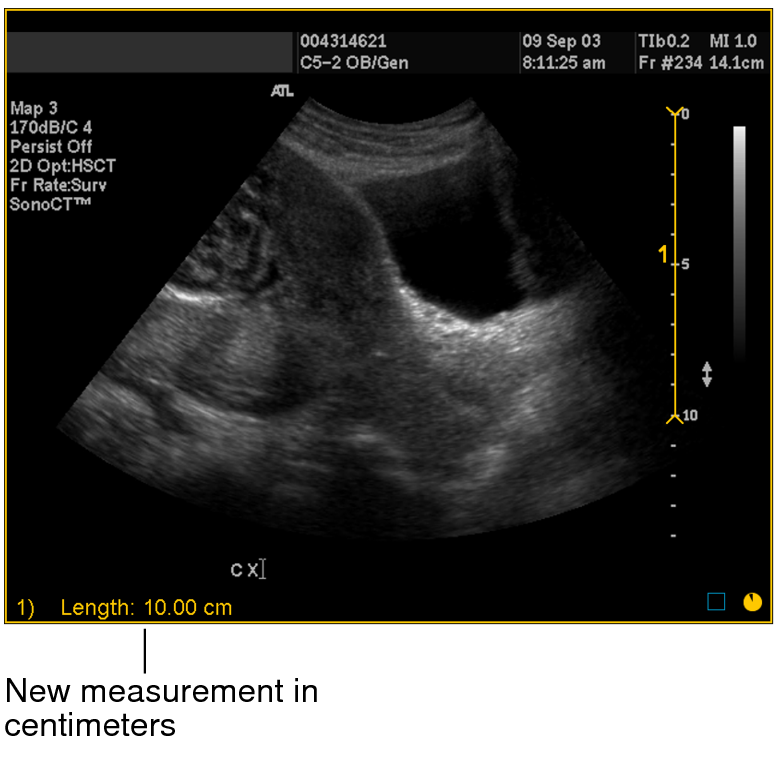

6. Click OK.

The image is calibrated and the length of the measurement now appears in centimeters. All subsequent linear, orthogonal, elliptical, and freehand region of interest measurements that you create on the image are calibrated according to this ratio.

New measurement